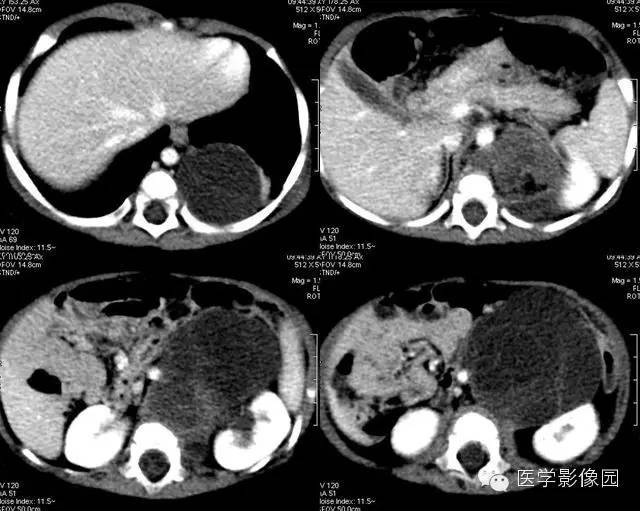

5——增强冠状位重建

6——增强冠状位重建

7——增强冠状位重建

畸胎瘤是由两个或三个原始胚层组织演化而来的胚胎性肿瘤,大体上囊性、实性或囊实性兼有。囊性畸胎瘤又称皮样囊肿,仅含表皮及其附属成分,基本上均为良性。实性畸胎瘤含有三个胚层成分。按组织学分类可分为良性畸胎瘤和恶性畸胎瘤。良性畸胎瘤由分化良好的成熟组织构成,故又称为成熟畸胎瘤,瘤体囊性部分多于实质部分,小儿中绝大部分均为良性畸胎瘤。恶性畸胎瘤由胚胎发生时期的未成熟组织构成,实质部分常多于囊性部分,恶性畸胎瘤在小儿中十分少见。小儿畸胎瘤以女性多见,男女之比约为1:3-4,腹部包块和腹胀为腹膜后畸胎瘤主要的临床表现,患儿一般状况良好。

恶性畸胎瘤瘤体以实体为主,病变边界模糊不清,可侵犯周围组织,肿块大小对鉴别良恶性意义不大。